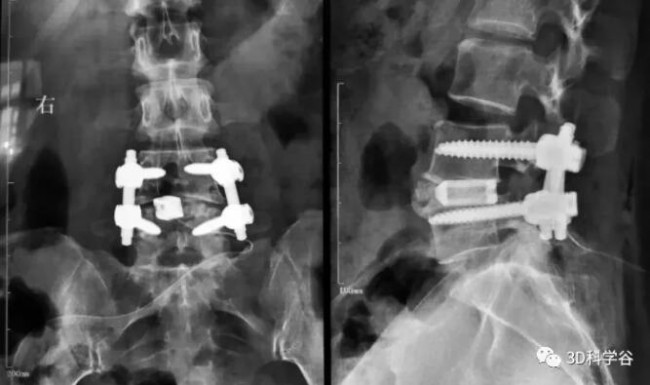

2021年9月,中诺恒康增材制造-3D打印 “椎间融合器” 获得国家药品监督管理局的批准上市。该产品由中诺恒康历时6年研发及临床验证,完成了具有自主知识产权创新产品的上市注册审批。这一产品将进一步推动我国3D打印钛合金脊柱植入物的商业化进程,并利于其在退行性脊柱疾病的临床应用。

这款获得批准的3D打印椎间融合器:孔径300-800μm,孔隙率70-80%,是国内首款无植骨窗使用增材制造工艺生产的融合器产品,具备良好的生物相容性、类松质骨的弹性模量,表面微孔结构提供良好的初始稳定性。

同时,该产品具备多型号、多规格能满足多种手术需求。产品使用符合融合器手术操作习惯,使得临床医生能够快速适应产品的术中植入及手术的推广。